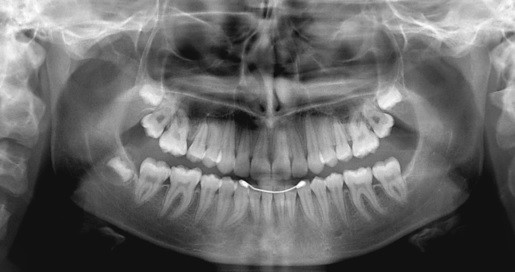

Radiografie Dentara Piata Muncii

Radiografie dentara piata muncii. 29 intre piata aviatorilor si piata charles de gaulle b dul iuliu maniu nr. 223 etaj 1 bucuresti statia piata muncii linia m1 b dul aviatorilor nr. Reteaua dental view cuprinde doua clinici in piata muncii si pe bld. Reteaua yts dental view cuprinde trei centre piata muncii aviatorilor si lujerului la care atat medicii cat si pacientii pot beneficia de o gama completa de servicii de radiografie si tomografie dentara 3d.

Yts dental este unul din principalii importatori si distribuitori de produse stomatologice din romania produse cu precadere pentru implantologia si chirurgia dentara. Yts dental view centru de radiologie si tomografie dentara bucuresti sos. Au strans cu grija datele si le au sintetizat in acest raport usor de urmarit. Yts dental view piata muncii yts dental view este cea mai moderna retea de centre de tomografie computerizata si radiologie dentara digitala din bucuresti avand servicii si echipamente radiologice ce raspund celor mai inalte standarde.